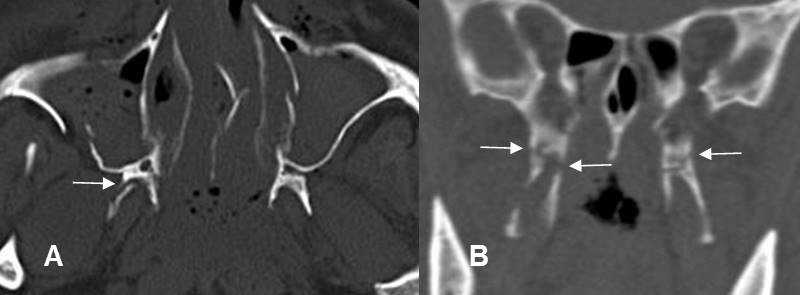

Fig 219. Láminas pterigoideas.

A: TAC axial y B: TAC reconstrucción coronal. Láminas pterigoideas normales.

Fig 220. Fractura de láminas pterigoideas.

A: TAC axial y B: TAC reconstrucción coronal. Fracturas de las láminas pterigoideas, hallazgo indispensable para hace el diagnóstico de fractura de Le Fort.